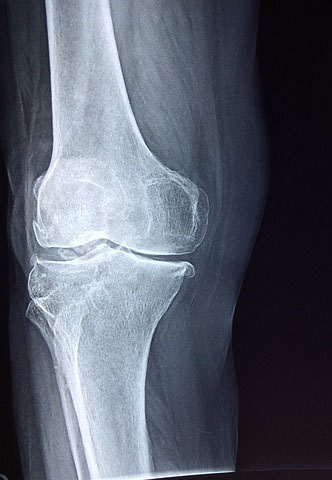

뼈와 뼈 사이을 연결해주고 움직임이 가능하게 하며 관절과 관절 사이에 위치하여 충격을 흡수해 주고 뼈가 부드럽게 움직이게 합니다.

콘드로이친은 관절과 연골을 분해하는 효소를 억제하는 기능이 있으며 새로운 연골 재생을 촉진해 줍니다.

연골을 분해하는 효소를 엘라스타아제라고 하는데 콘드로이친은 이 엘라스타아제를 억제하여 연골이 감소하는 것을 막아줍니다.

2. 관절 통증 감소와 보행 능력 향상

다양한 연구에서 콘드로이친을 섭취했을때 관절 통증이 감소하고 보행 능력이 향상되는 것을 확인했다고 합니다.